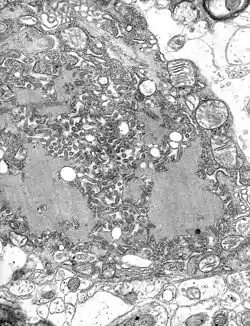

![]() | |